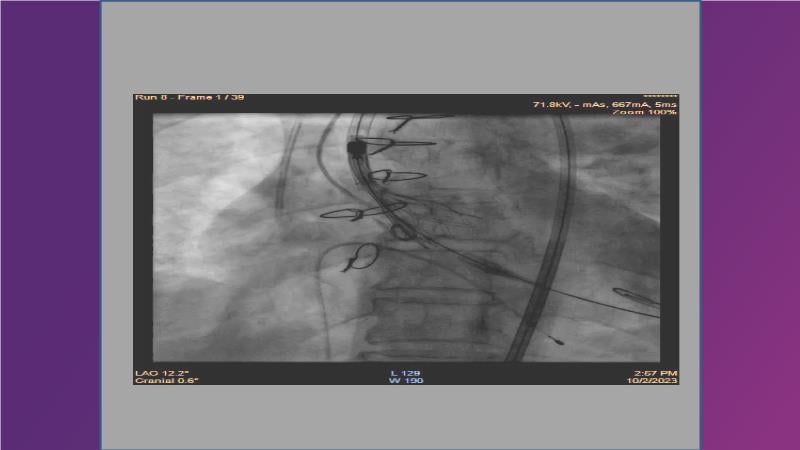

Gain expertise in selecting the appropriate TAVI device for achieving stable deployment in a 90-degree horizontal aorta. Discover techniques for ensuring smooth deliverability, particularly when navigating through tight and tortuous anatomies. Additionally, learn strategies to prepare for future coronary access, irrespective of the height of the left or right coronaries.

• To learn how to select your TAVI device in order to achieve stable deployment in 90 degrees horizontal aorta

• To witness smooth deliverabilty even crossing tight and tortous anatomy